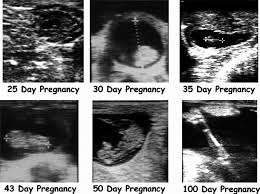

The predominant british, irish, and commonwealth spelling is foetus, which has been in use since at least 1594. (used chiefly of viviparous mammals) the young of an animal in the womb or egg, especially in the later stages of development when the body structures are in the recognizable form of its kind, in humans after the end of the second month of gestation. A human being or animal as it is developing in the uterus before birth, after the organs have started to form. Noun c us. The plural form of fetus is fetuses or feti.